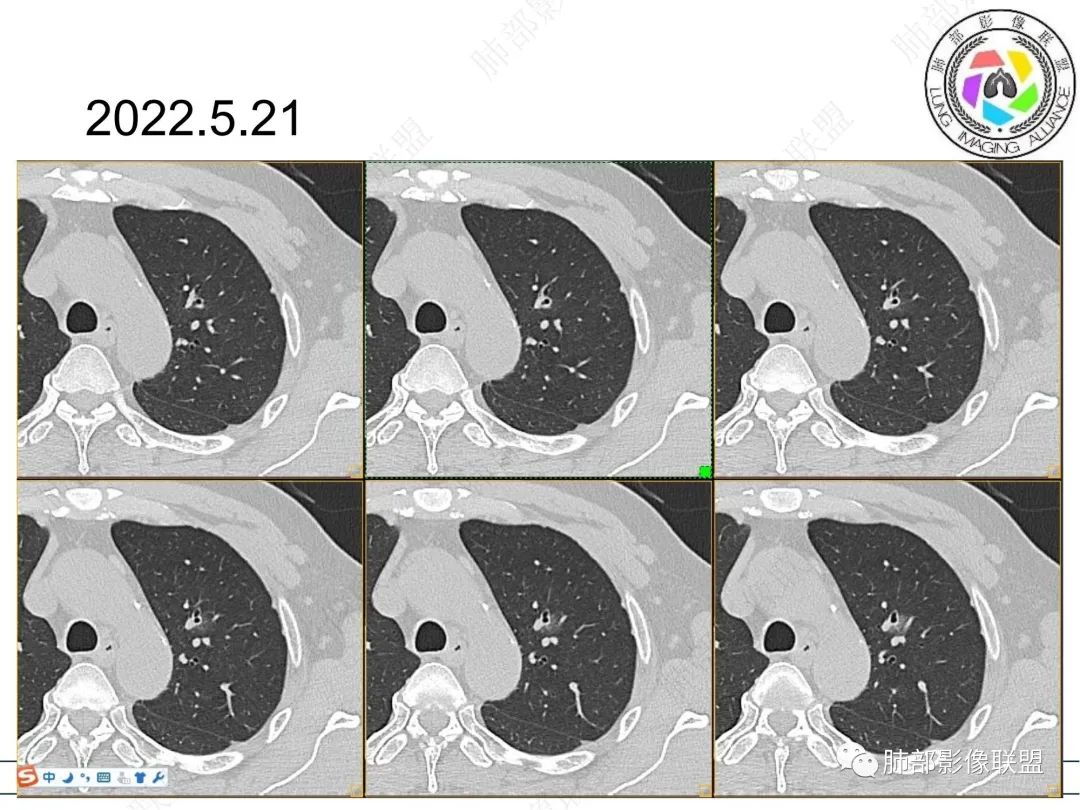

我标示一下,说一下个人的想法

初始病灶应该是这里

病灶朝前、外侧进展

病灶包括两部分

1、实性2、周围GGO

目前看支气管通畅

实性部分强化明显,边缘平直